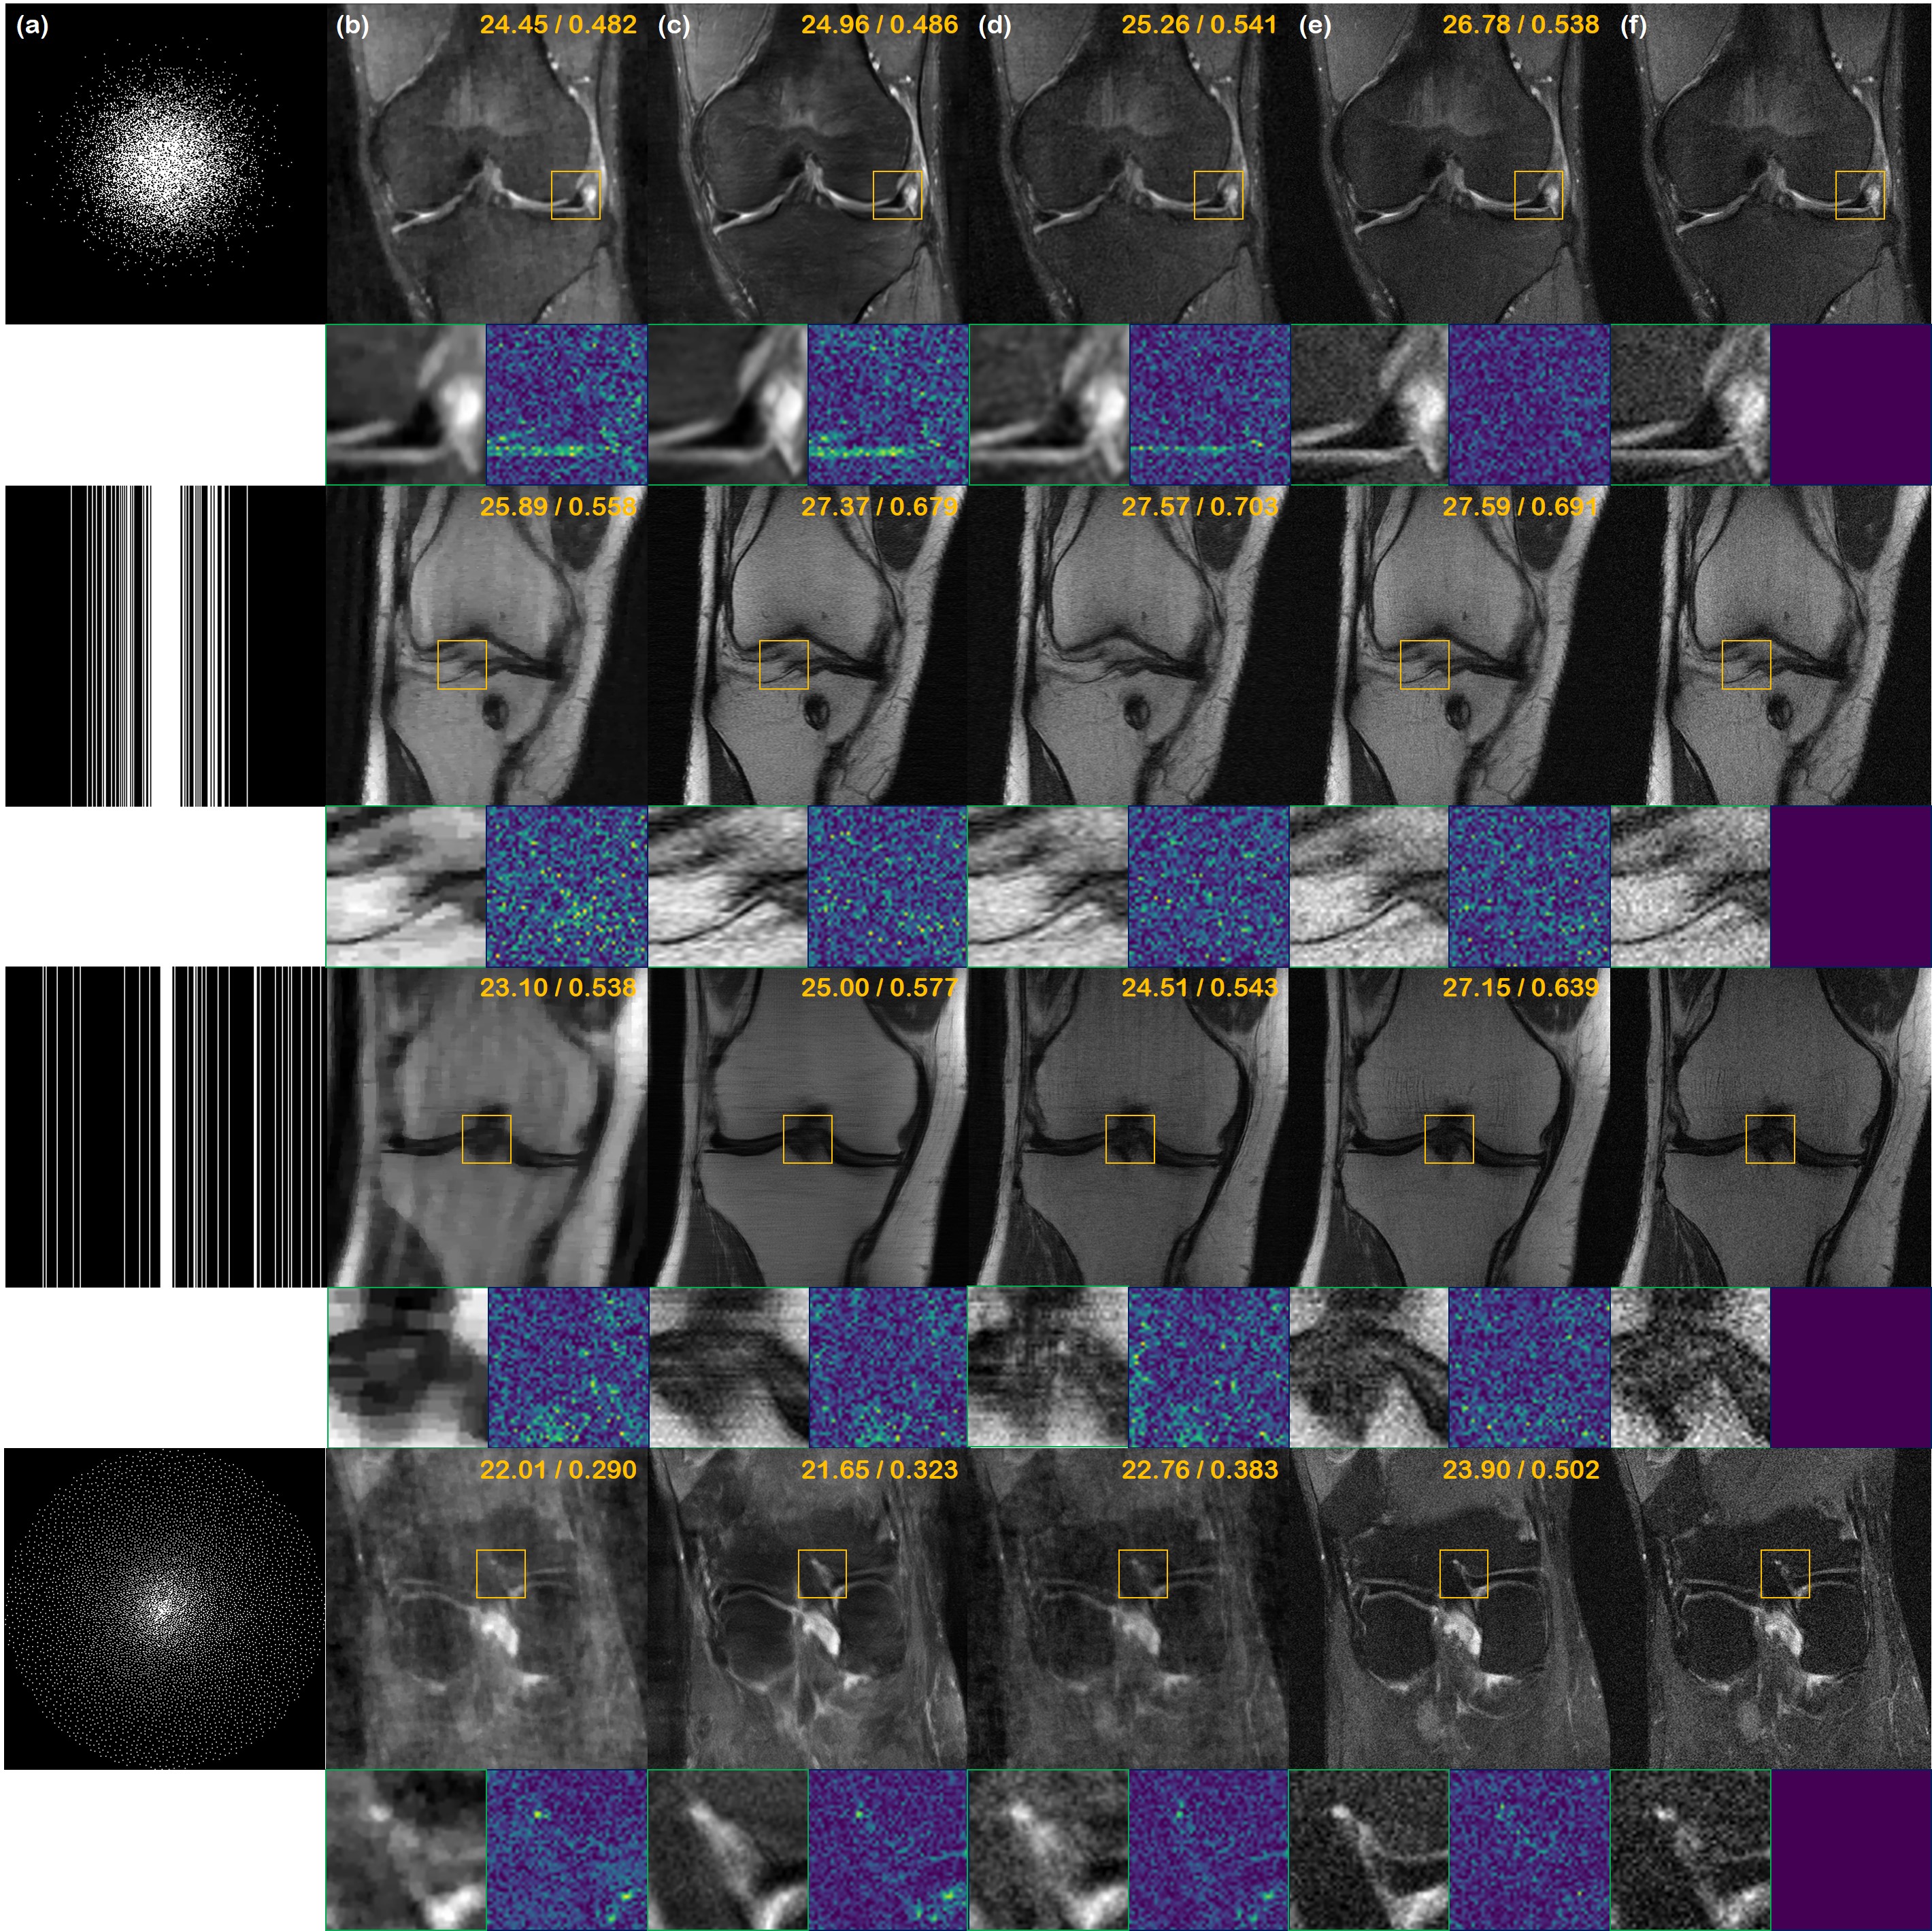

Refer to caption

Fig. 4: Single-coil complex-valued image reconstruction results. (a) Sub-sampling mask used to generate under-sampled image, (b) TV, (c) supervised learning (U-Net) (d) DuDoRNet [68], (e) proposed method, and (f) ground truth. 1stst{}^{\text{st}} row: 2D ×8absent8\times 8 Gaussian random sampling, 2ndnd{}^{\text{nd}} row: 1D ×4absent4\times 4 Gaussian random sampling, 3rdrd{}^{\text{rd}} row: 1D ×8absent8\times 8 uniform random sampling, 4thth{}^{\text{th}} row: ×15absent15\times 15 variable density poisson disk sampling. Green box: Zoom in version of the indicated yellow box, Blue box: Difference magnitude of the inset (in Viridis colormap). Yellow numbers in the upper right corner indicate PSNR [db], and SSIM, respectively.

5.2 Complex-valued Single-coil Reconstruction

In Fig. 4, we illustrate the reconstruction results of the proposed method using Algorithm 3, along with the baseline comparisons. In the first row, we have ×8absent8\times 8 2D Gaussian random sampling acceleration. The proposed method performs a very accurate reconstruction, without inducing any additional blurriness from the reconstruction process. TV, supervised U-Net, and DuDoRNet fall largely behind the proposed method both in terms of perceptual quality and quantitative metrics.

In the second row, we have ×4absent4\times 4 1D Gaussian random sampling (8% ACS region) acceleration. Again, the proposed method reconstructs the aliased image with high accuracy and has higher quality than the comparison methods.

The third row shows ×8absent8\times 8 1D uniform random sampling (4% ACS region). The proposed method is still able to reconstruct the aliased image with virtually no degradation in the high-frequency details. On the other hand, supervised U-Net reconstruction produces horizontal strip artifacts, hampering the visual quality. DuDoRNet does not remove the aliasing artifacts completely. TV hardly produces satisfactory results. The final row shows reconstructions with ×\times15 VD poisson sampling. Due to the bias toward 1D sampling patterns, both U-Net and DuDoRNet produce unsatisfactory results with washed-out details. Our method is able to preserve sharp edges and texture, clearly depicting the anatomical structure. Quantitative metrics in Table 1 also confirm the superiority.

As mentioned earlier, all the results depicted in Fig. 4 were generated using the single score function, trained with DICOM images only. This means that the model has never seen complex-valued data before, and yet the quality of reconstruction is surprisingly high. This is an important advantage of our model over conventional DL methods. Most DL methods require raw k𝑘k-space data to train the network, and this is hard to achieve since most raw data are discarded after the scan [65]. In contrast, DICOM images are relatively much easier to collect, and this enables practitioners to collect a large database for training.